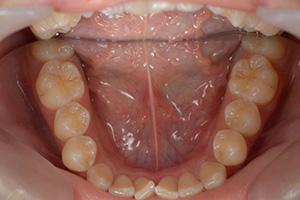

矯正治療のCASE 05

Before

After

-

- 主訴

- 歯並びがガタガタしていて清掃しにくい

- 治療内容

- ラビアル矯正(表側)

抜歯あり

- 治療費用

- 88万円~(税込)

- 治療期間

- 20か月

【リスク・副作用】

歯の痛み、口内炎、歯磨きがしにくいことによるむし歯や歯周病のリスク、歯根吸収や歯の変色、後戻りなどの副作用があります。